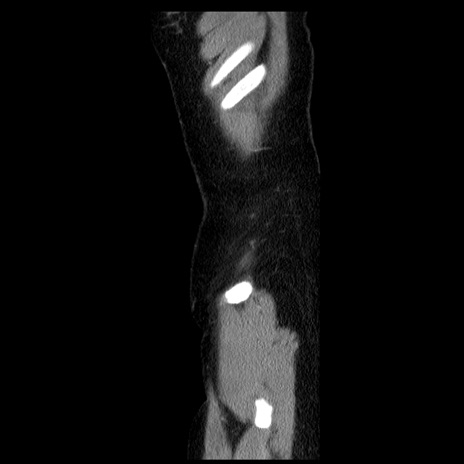

横断像